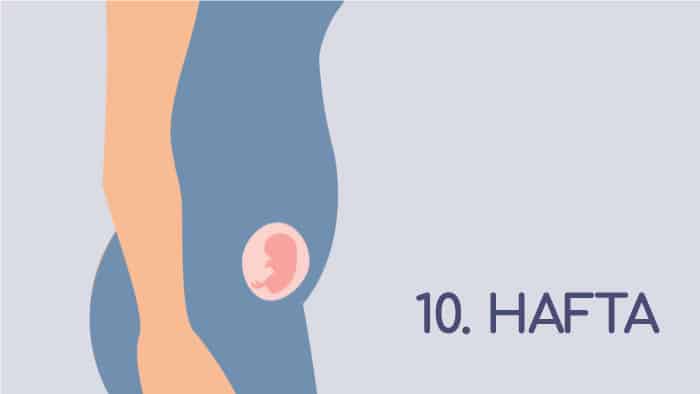

10 haftalık gebelik aynı zamanda embriyo döneminin de sonu. Bu haftadan sonra anne karnındaki minik kuzular fetüs ismi ile anılıyormuş. 11. Haftadan doğuma kadar sürecek fetal dönemde, embriyonal dönemde oluşan organ sistemleri gelişiyormuş.

10 Haftalık Gebelik Görüntüsü

Önce hücre topu, sonra minik bir deniz atı gibi görünen bebekler bu haftadan sonra bebek görünümüne daha da yaklaşıyor. Omurga uzantısı kuyruk kayboluyor, vücudunun 3’te biri büyüklüğünde olan baş ve ense zamanla normla bir görünüme kavuşuyormuş.

Geçtiğimiz hafta bir zeytin tanesi kadar olan minikler 10 haftalık gebelik döneminde ortalama 3,1-4,2 cm uzunluğa erişiyor. Ağırlıkları ise yaklaşık 5 gr. Yani bu hafta bebişlere minik bir çilek diyebiliriz.

10 haftalık gebelik döneminde bebeklerde olan değişimleri şöyle sıralayabiliriz;

- Tırnakları oluşmaya başladı,

- Parmak izi oluşuyor,

- Dış kulak son şeklini almak üzere,

- Tendonlar, bacak kaslarını kemiklere bağlıyor ve diz eklemi belirginleşiyor,

- Eller ve ayaklar artık bir araya getirilip birleştirilebiliyor,

- İlk tekmelemeler başladı (ancak henüz hissedememeniz çok normal. Minik tekmeleri hissetmek için biraz daha beklemeniz gerekiyor)

- Beyin gelişimi de son hız devam ediyor. Dakikada 250 bin nöron üretiyor,

- Minik diş tomurcukları oluşmaya başlıyor,

- Böbreklerde idrarı süzen ana filtreleme birimleri oluşmaya başlıyor,

- Kalın bağırsaklarında, bağırsak hareketleri başladı,

- Erkek bebekte testisler, erkeklik hormonu testosteron üretimine başladı bile,

- Gözkapakları hızlıca oluşmaya başlıyor ve birleşerek kapanıyor.